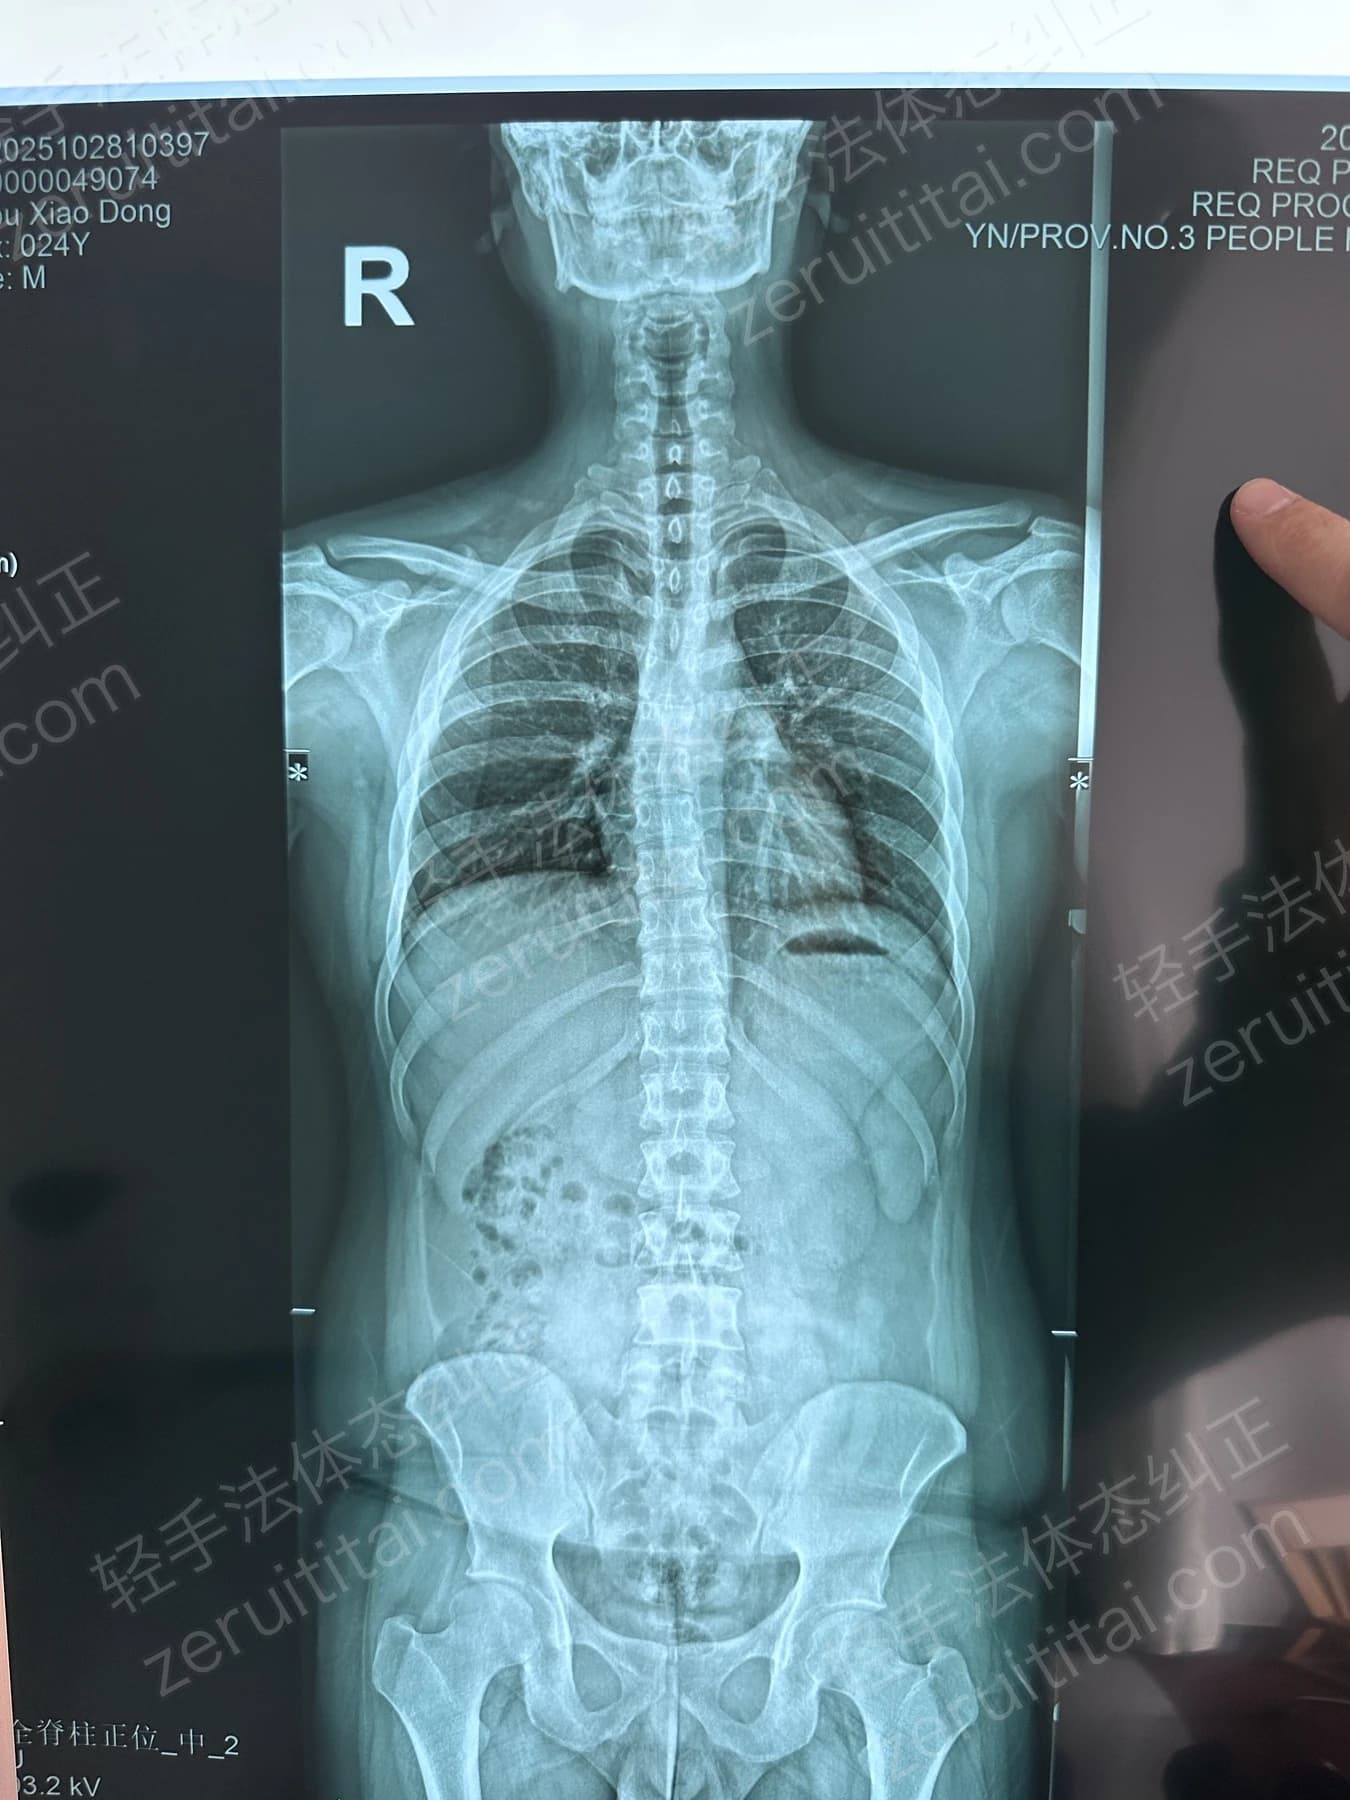

2022.09.27

第 2 次记录